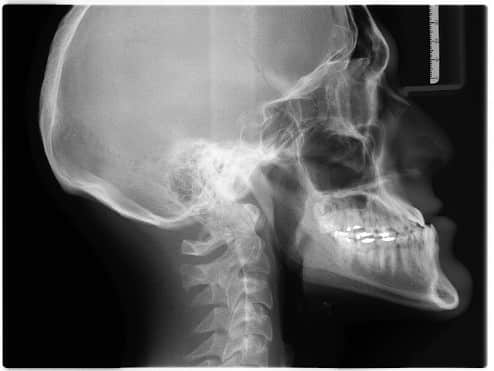

整形外科・病院での交通事故後の診断について

交通事故に遭われた際には、まず整形外科などの病院に行き診断を受けることが必要ですが、事故日から診断を受けた日までの期間が開いてしまうと、補償を受けられなくなることがあるので注意してください。

人身事故で補償を受ける上では、傷害部位(お怪我の箇所)の交通事故との因果関係がとても重要になります。事故日から診断までの日数が開いてしまうと、「因果関係を証明できない」と判断されてしまう可能性がありますので、注意しましょう。